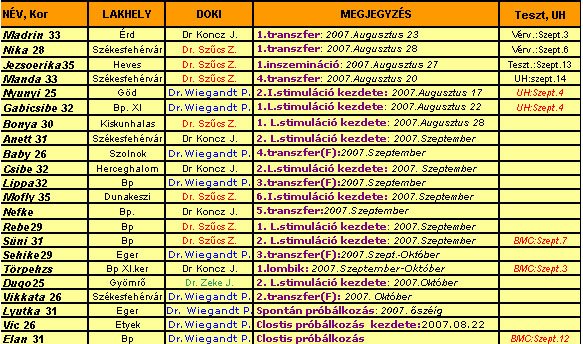

No, az új adatokat beírtam a táblába, már csak sorba rakok mindenkit, és dobok egyet!